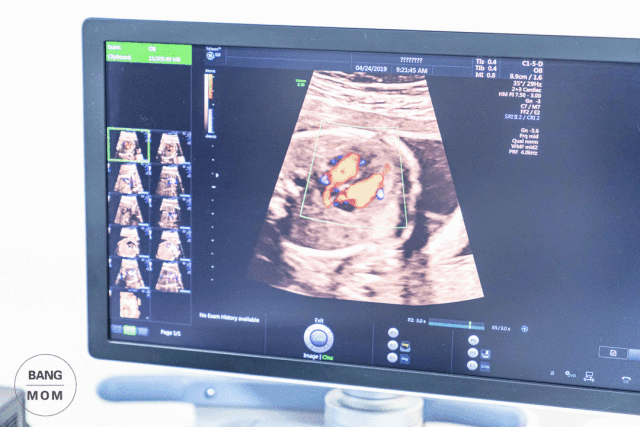

| 青岛妇女儿童医院与青岛同安妇婴医院的B超检查结果 | 这是同一位妈妈,分别在同安妇婴医院和妇女儿童医院做的19周孕期超声。一份是Ⅰ级筛查,一份是Ⅲ级筛查。 比对一下可以看出,其结论都是一样的:胎儿心脏发育异常,胎儿心脏法络氏四联症。 探访科室 19周左右胎儿的小心脏大概只有成人食指的指肚大小,要在这么小的器官里看清腔室、血管等微小的细节,需要超声医生有丰富的经验和足够的细心。

检查过程中扫过胎儿心脏时,超声科的医生敏锐的发现了一点血流异常,为了确保无误,又进行详细检查。再三确认后,结果证实了医生的最初判断——胎儿心脏法络氏四联症。

同安产科与超声科又进行联合的会诊,建议这位孕妈到有资质的产前诊断中心进行Ⅲ级检查,以确保检查的准确性。